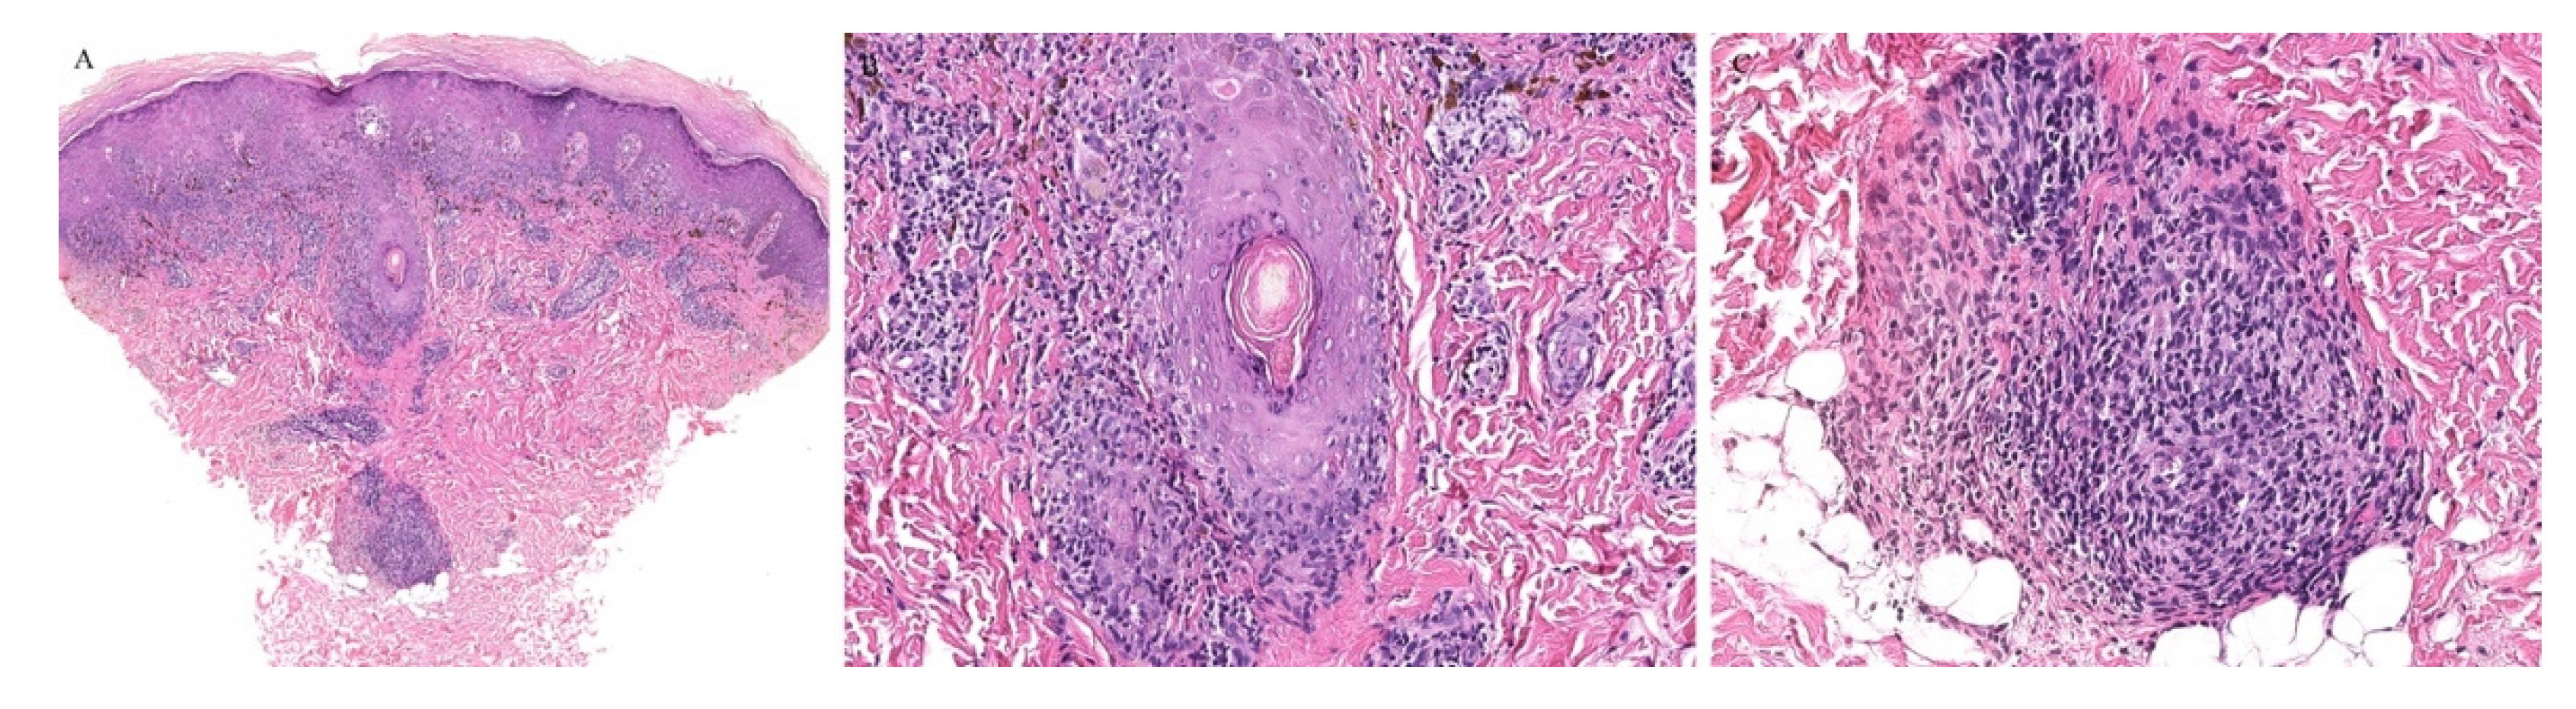

Follicular MF is a variant of MF whereby the atypical lymphocytes infiltrate the hair follicle (Figure 10). Clinically, this condition is mainly seen over the head and neck areas and may be associated with alopecia.

Figure 10.

(A–C) Histopathology of follicular mycosis fungoides.

Histopathologically, follicular MF is usually characterized by a mildly atypical, variably pleomorphic lymphocytic infiltrate with perifollicular accentuation with associated cysts in up to 36% of cases. The epidermis is commonly spared. Mucin deposits in the follicular epithelium (follicular mucinosis) characterizes FMF and has been described in around 75% of cases. In addition, concomitant perieccrine infiltrates have been reported in 4% to 33% of cases. Distinguishing between follicular MF and follicular mucinosis may be challenging, however necessary, as the two entities vary in outcomes and prognosis. In the case of follicular mucinosis, follicular involvement may be observed in the form of mucinous degeneration of the hair follicle [45]. Follicular mucinosis in the absence of mycosis fungoides confers a benign course. However, in follicular MF, intrafollicular mucin deposition secondary to the lymphocytic infiltrate of the follicular epithelium can be observed [46].

Syringotropic MF has also been described with marked eccrine gland and duct epitheliotropism (Figure 11). Clinically, this may appear as a solitary lesion or multiple localized lesions. Alopecia has also been described in syringotropic MF. In addition, syringometaplasia has also been reported in a few cases [47].

Figure 11.

(A–C) Histopathology of syringotropic mycosis fungoides.

Involvement of the hair follicle and eccrine glands have been reported concomitantly within the same biopsy specimens. In one study of patients with folliculotropic MF, eccrine involvement was reported in up to 56% of the cases [46]. In addition, two cases of concomitant folliculotropic and syringotropic MF without any epidermal involvement have been described, illustrating a major pitfall in recognizing MF without the classical features of epidermotropism [48].